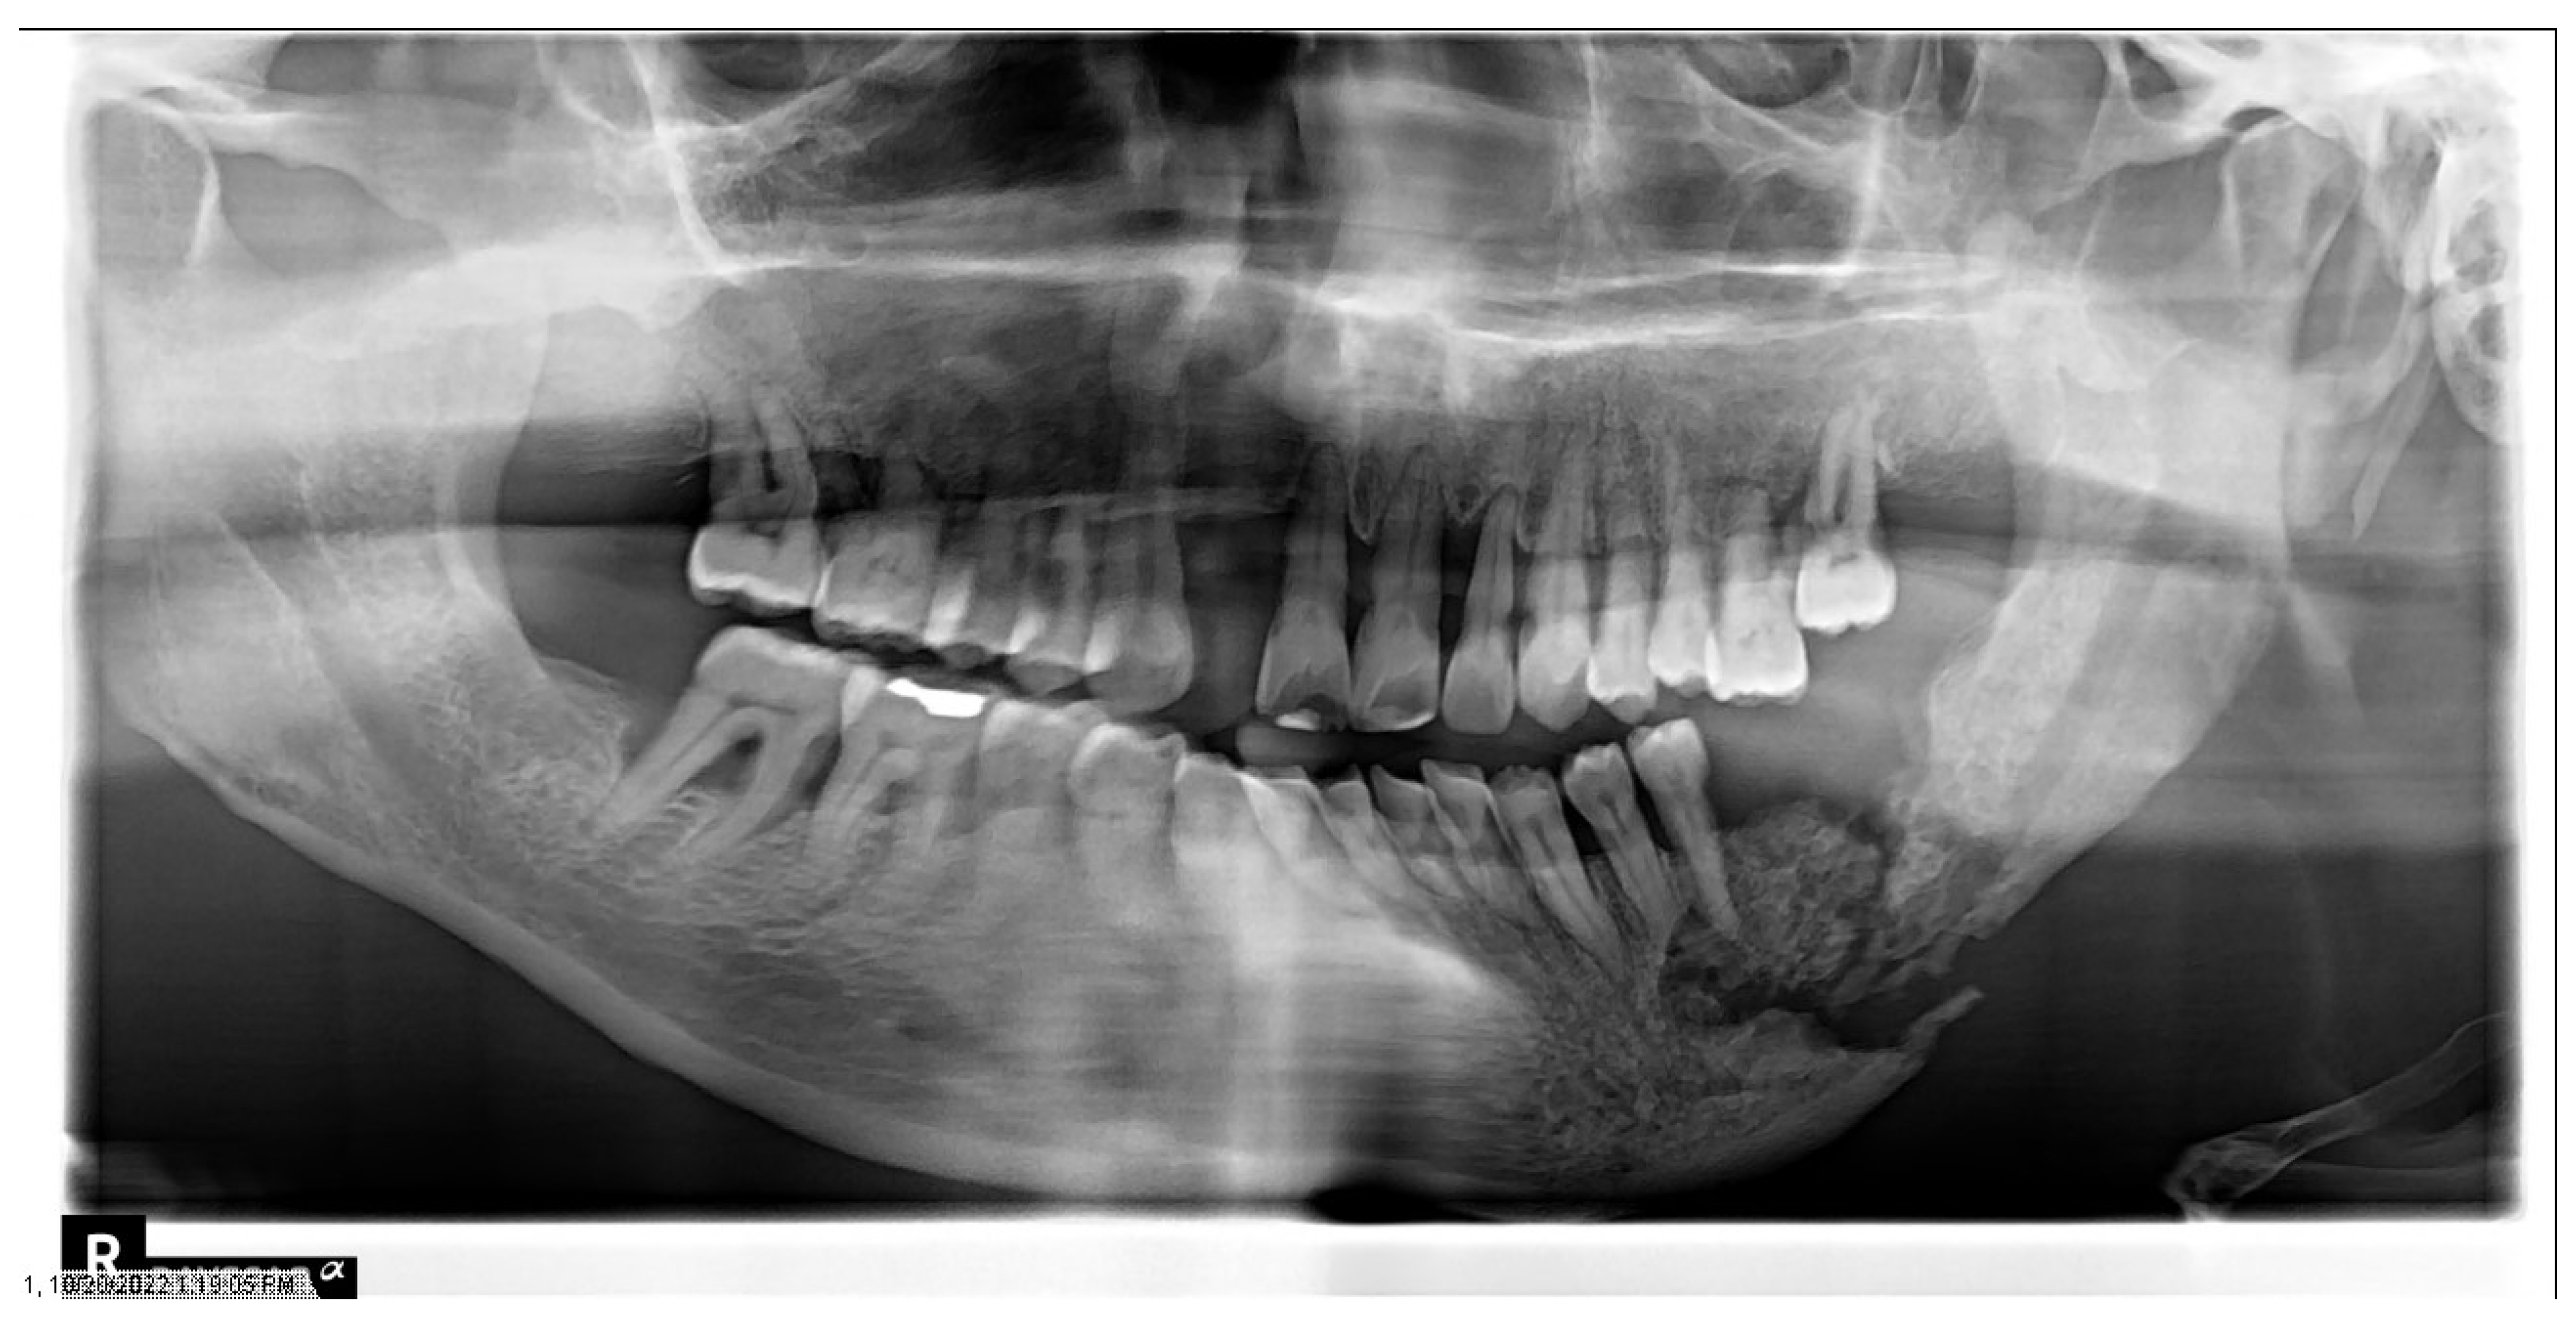

1.4. Osteoradionecrosis

Prevention and Management of Osteoradionecrosis